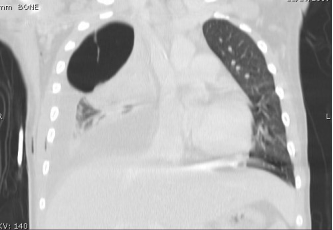

胸部CT提示在Lucy的右肺上叶有一巨大(7×7×6 cm)多房囊性病变,呈气-液平面(图2、图3)。

图2,来自medscape

图3,来自medscape